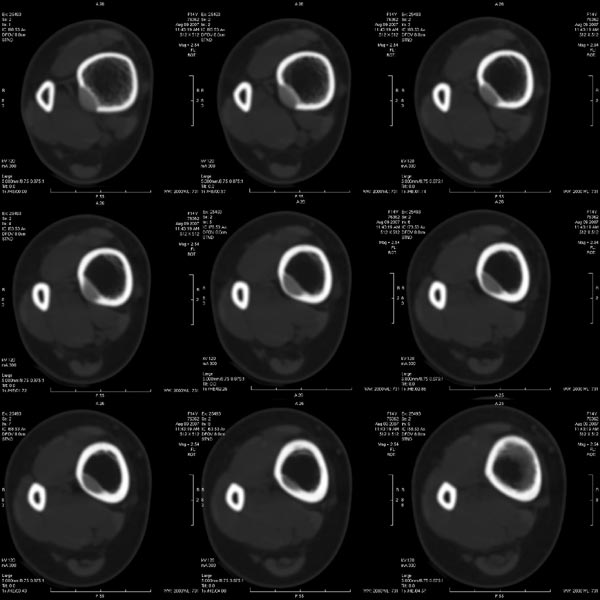

胫骨中段皮质内环绕并突入髓腔膨胀性生长的软组织密度病灶,内缘粗糙,外缘光滑无中断,病灶内可见小点状钙化.未见骨膜反应及瘤骨;软组织显示如常,未见肿块及异常密度.

右胫骨中段囊性、膨胀性改变,病变呈中心性,沿骨的纵轴生长,病变区骨皮质明显变薄,骨包壳完整,无中断,病变边缘无明显硬化,未见明显骨膜反应,周围软组织无肿胀。首先肯定的是骨良性病变(良性骨肿瘤或肿瘤样病变。有以下几种可能:

1 骨囊肿:发生于骨干的囊肿,可沿髓腔的长轴发展,在髓腔形成长囊状骨折破坏区,但骨囊肿病变周围一般都有明显边缘硬化,易发生病理性骨折,这点不支持。

2 动脉瘤样骨囊肿:好发于长骨干骺端,多偏心生长于骨干的一侧,易多囊、分隔、有嵴(皂泡样),中心型可沿纵轴生长,呈溶骨性囊样,但囊内也多含粗或细的骨小梁,边缘也有硬化环包绕。也不太支持。

4 骨巨细胞瘤:好发于骨端,偏心性向骨的横轴生长多见,呈皂泡样,但也有较少见的发生于骨干的呈中心性生长的巨细胞瘤,破坏边缘无明显硬化边,此点符合。

5 骨纤维异常增殖症:可有囊状膨胀性、磨玻璃样、丝瓜瓤样及虫蚀状多种表现,囊状膨胀性可有类似改变,但范围一般较广,也常绕硬化环。

总之,我感觉骨肿瘤及肿瘤样变鉴别诊断很困难,有时病变表现不典型时影像很难确诊,此病例我的诊断是:骨巨细胞瘤>骨血管瘤>骨纤。